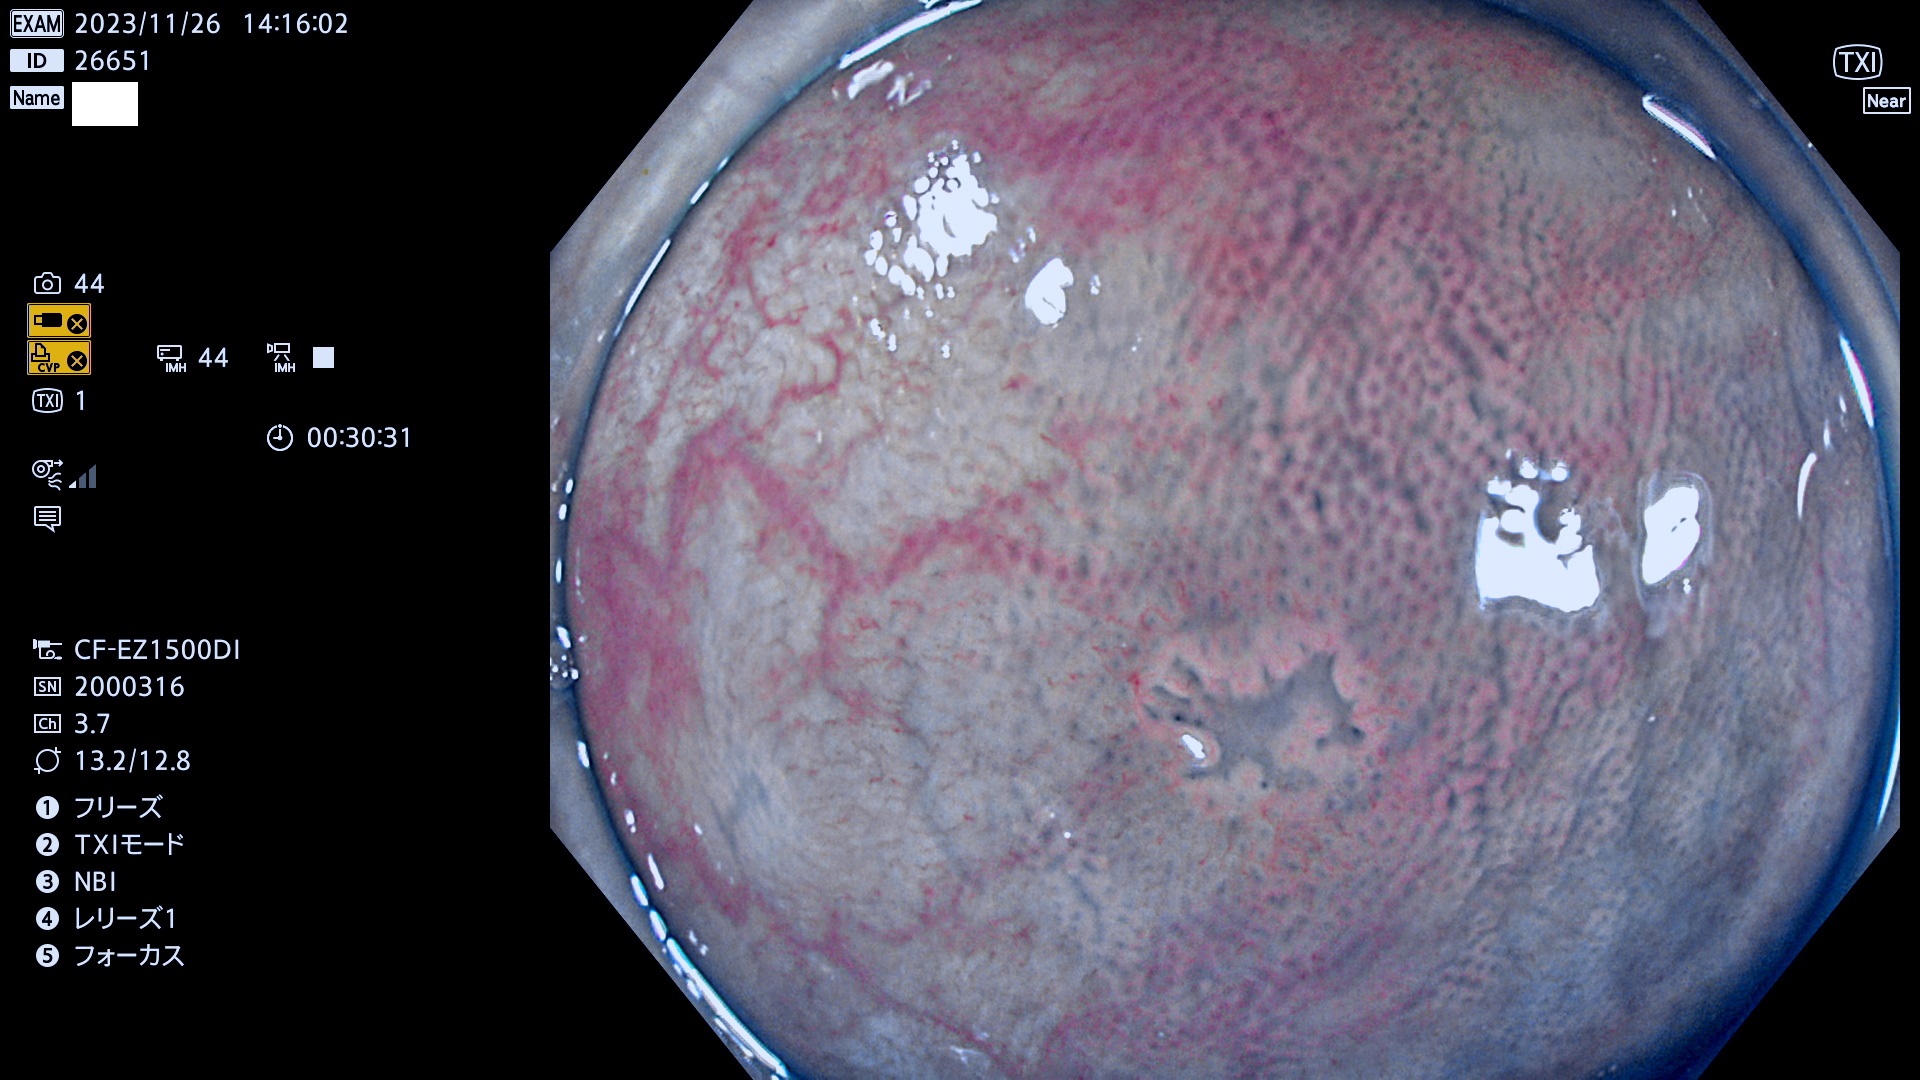

表面型腺腫(Flat Adenoma)の中で、完全に平坦な物をUb、陥凹している物をUcと呼びます。平坦隆起型(Ua)よりも、発見が難しく危険な病変です。このタイプは「内視鏡後・大腸癌の重要犯人」であり、この発見率は「腺腫発見率」よりも、重要な意味があります。

毎週の検査(木・金・土・日)に発見されたUb、Uc型・腺腫を、その週の日曜の夜にUPし1週間、提示します。

抽出の対象期間 2023年11月23日(木)〜11月26(日)の4日間(48件の検査)8件